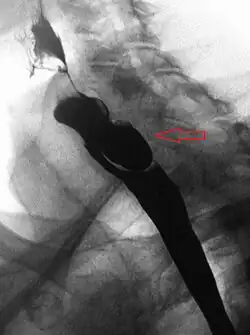

A combination of the simple barium swallow and a thorough endoscopy will normally confirm the diverticulum.[4]